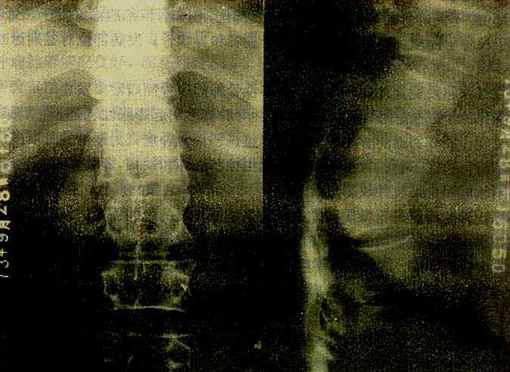

(四)脊椎结核 脊椎结核(tubercrlosis of spine)是骨关节结核的最常见者,好发于儿童和青年。以腰椎最多。病变好累及相邻的两个椎体,附件较少受累。临床上,常有脊柱活动受限,局部疼痛,冷性脓肿和窦道形成。还可发生脊柱变形和脊髓受压症状。

椎体结核主要引起骨松质的破坏。由于骨质破坏和脊柱承重的关系,椎体塌陷变扁或呈楔形。由于病变开始多累及椎体的上下缘及邻近软骨板,较早就引起软骨板破坏,而侵入椎间盘,使椎间隙变窄,甚至消失和椎体互相嵌入融合而难于分辨(图2-1-22)。病变广泛。常出现后突变形。病变在破坏骨质时可产生大量干酪样物质流入脊柱周围软组织中而形成冷性脓肿。腰椎结核干酪样物质顺一侧或两侧腰大肌引流,称为腰大肌脓肿,表现为腰大肌轮廓不清或呈弧形突出。胸椎结核的脓肿在胸椎两旁,形成椎旁脓肿,表现为局限性梭形软组织肿胀,边缘清楚。在颈椎,则使咽后壁软组织增厚,并呈弧形前突,侧位上易于观察。冷性脓肿较久可有不规则形钙化。

图2-1-22 脊椎结核

胸12与腰1椎体破坏、融合,两椎体间不见椎间隙,于该处有后突变形,

于右侧可见腰大肌脓肿,并有钙化

总之,脊椎结核的主要X线变化是椎体骨质破坏,变形,椎间隙变窄或消失和冷性脓肿的出现。同椎体压缩性骨折的楔状变形一般不难鉴别,后者无骨质破坏,椎间隙不变窄,更无冷性脓肿表现,而且有清楚的外伤史。